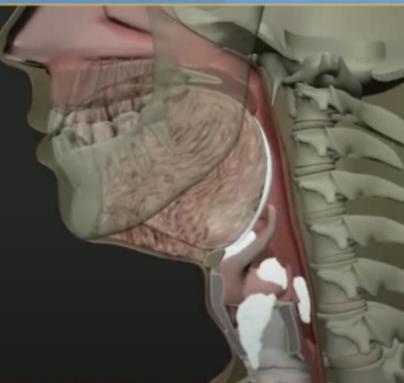

Oral phase

Pharyngeal Phase

pharyngeal/e sophageal phases

Esophageal phase

Anatomical & Functional Differences in Swallowing: Children vs. Adults